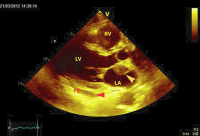

Echo

Abbildung 6: Apikaler Vierkammerblick: Raumforderung im linken und rechten Vorhof (Pfeile), kleiner Perikarderguss